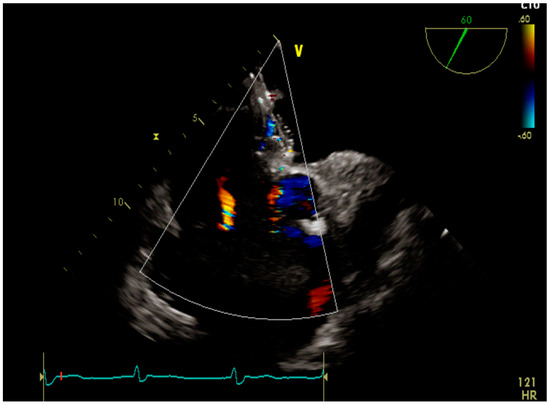

4.1. Case 1

4.2. Case 2

4.3. Case 3